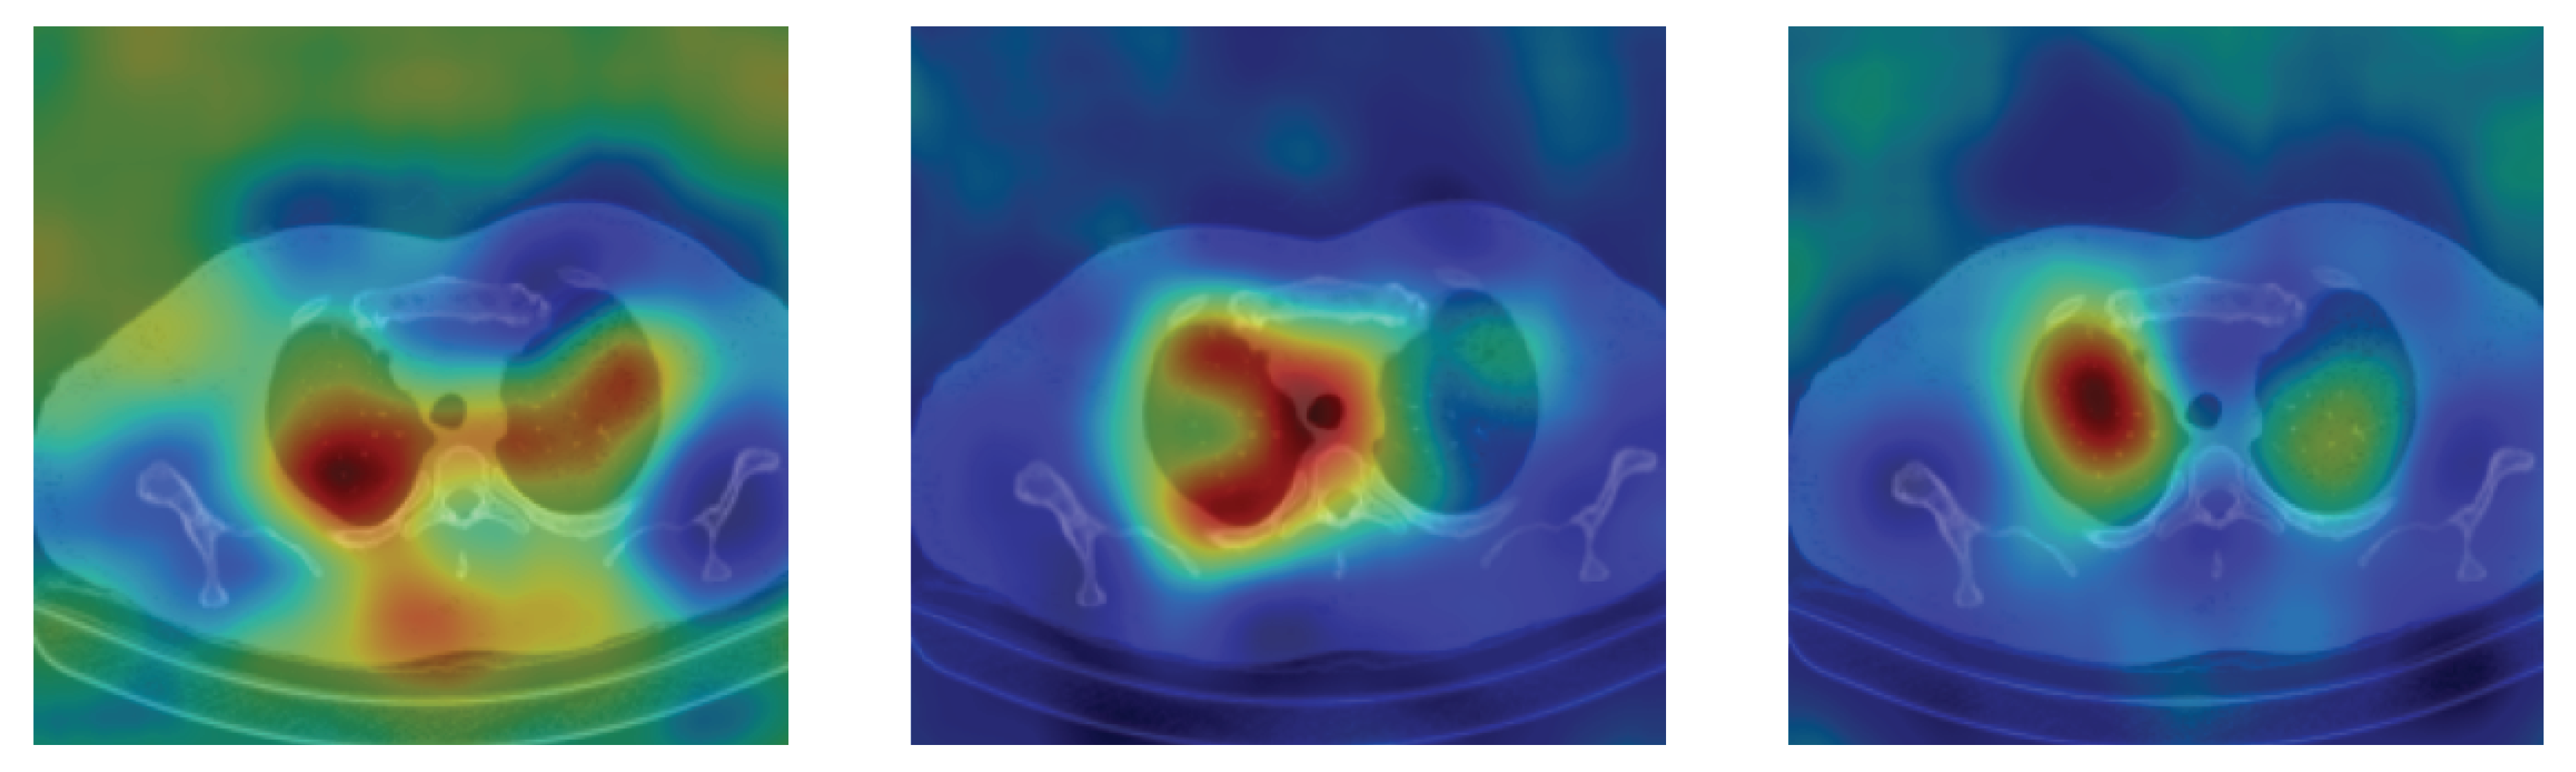

4.5. Heat Map

To have more intuition about the most important lung regions that the CNN architectures consider to classify the slice images, we used the randomized input sampling for explanations (RISE) approach [37]. Figure 13, Figure 14 and Figure 15 consist of two heat map examples of COVID-19, Cap, and normal cases, respectively. In the first example from Figure 13, we notice that despite the lung segmentation being not fully correct (it misses a considerable part of the infected region), the four CNN architectures gave more importance to the infected regions and to the lung regions in general. In the second example from Figure 13, we observe that the lung lobes were precisely segmented, and the heat maps of the four CNN architectures were well defined the infected regions, especially the Wide-Resnet-50 architecture. From both Cap examples in Figure 14, we notice that despite the lung segmentation missing considerable infected parts as well as the lung lobe regions, the heat maps of all CNN architectures give more importance to the infected region and to the lung lobes in general. This proves that the trained CNN architecture is able to define the regions of interest even when the lung lobes segmentation is not good. For the normal slice examples in Figure 15, the trained CNN architectures gave more importance to the lung lobes, especially the lower region, since the infection usually occurs there. The heat maps of COVID-19, Cap, and normal cases prove that the CNN architectures learned precisely where to look to identify the infection from the slice images.

Figure 14.

RISE heat map examples of Cap slice image using the trained multi-tasks CNN architectures (ResneXt-50, Densenet-161, Inception-v3, and Wide-Resnet-50). The first example is shown in the first two rows, where the images represent the input slice image and segmented lung lobes results, followed by the heat maps of ResneXt-50, Densenet-161, Inception-v3, and Wide-Resnet-50, respectively. The second example is in rows 3 and 4.